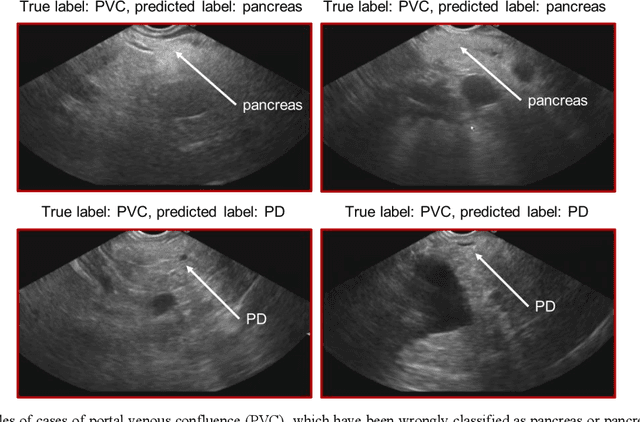

Abstract:Ultrasound imaging is a commonly used technology for visualising patient anatomy in real-time during diagnostic and therapeutic procedures. High operator dependency and low reproducibility make ultrasound imaging and interpretation challenging with a steep learning curve. Automatic image classification using deep learning has the potential to overcome some of these challenges by supporting ultrasound training in novices, as well as aiding ultrasound image interpretation in patient with complex pathology for more experienced practitioners. However, the use of deep learning methods requires a large amount of data in order to provide accurate results. Labelling large ultrasound datasets is a challenging task because labels are retrospectively assigned to 2D images without the 3D spatial context available in vivo or that would be inferred while visually tracking structures between frames during the procedure. In this work, we propose a multi-modal convolutional neural network (CNN) architecture that labels endoscopic ultrasound (EUS) images from raw verbal comments provided by a clinician during the procedure. We use a CNN composed of two branches, one for voice data and another for image data, which are joined to predict image labels from the spoken names of anatomical landmarks. The network was trained using recorded verbal comments from expert operators. Our results show a prediction accuracy of 76% at image level on a dataset with 5 different labels. We conclude that the addition of spoken commentaries can increase the performance of ultrasound image classification, and eliminate the burden of manually labelling large EUS datasets necessary for deep learning applications.